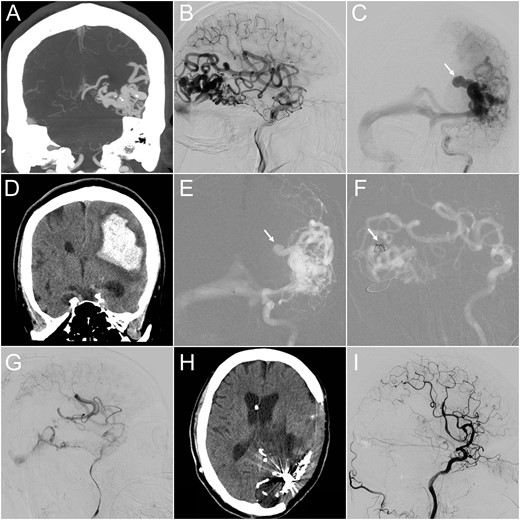

(A) CT angiography (coronal view) revealed a 4-cm AVM at the left temporo-occipital region. (B and C) Lateral projection of early (B) and frontal projection of late (C) arterial phase of left internal carotid angiograms demonstrated a high-flow AVM and a co-existing venous aneurysm on the draining vein (arrow), which ruptured 1 month after this angiographic study. (D) Emergency CT performed after the patient lost consciousness revealed a massive parenchymal hemorrhage at the left parieto-temporal region. (E and F) Microcatheter was advanced into the ruptured venous aneurysm, where detachable coils were deployed (arrow). (G) Following targeted embolization, the size and flow of the residual AVM were significantly reduced. (H) Follow-up CT 3 months later showed total resolution of the brain edema. (I) The follow-up internal carotid angiogram also demonstrated complete angiographic regression of the residual AVM.